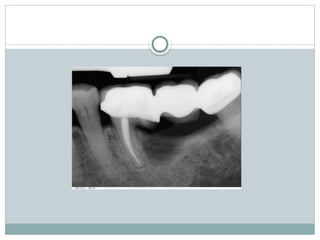

Diagnosis

Clinical diagnosis

Radiographic diagnosis

 Radiograph may or may not depict the

furcation involvement

Grade-III

 Bone is not attached to the dome of

the furcation

 Early grade III opening may be filled

with soft tissue and may not be visible

Grade-lV:

 Interdental bone is completely

destroyed

 Soft tissue is resided completely, so

furcation opening is clinically visible

 Tunnel exist between the roots